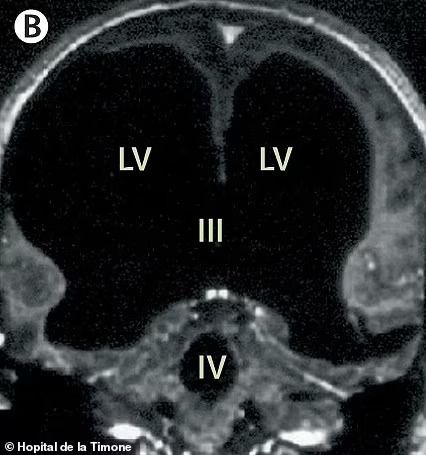

Šuntas vėliau buvo pašalintas, kai jam buvo 14 metų. Atlikus kompiuterinės tomografijos (KT) ir magnetinio rezonanso tomografijos (MRT) skenavimus, gydytojai buvo šokiruoti pamatę didžiulę skysčio ertmę ten, kur turėjo būti smegenys.

Nuotraukose, pasidalintose medicinos žurnale „The Lancet“, pagrindinė vyro smegenų sritis atrodo juoda, matosi, kur kaupėsi skystis.

Paciento smegenyse esantys nutekėjimo vamzdeliai susiaurėjo, dėl ko per dešimtmečius susikaupė skysčio perteklius.

Dėl to jo smegenys buvo suspaustos į ploną sluoksnį, spaudžiamą prie kaukolės krašto.